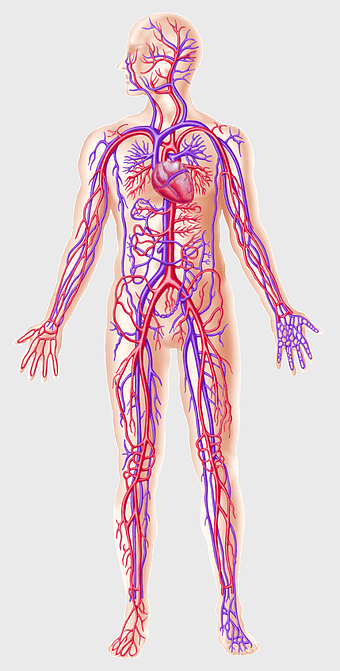

human circulatory system, blood vessel anatomy, weight loss exercise benefits, heart and artery health, vascular network visualization, cardiovascular health illustration, systemic circulation diagram -